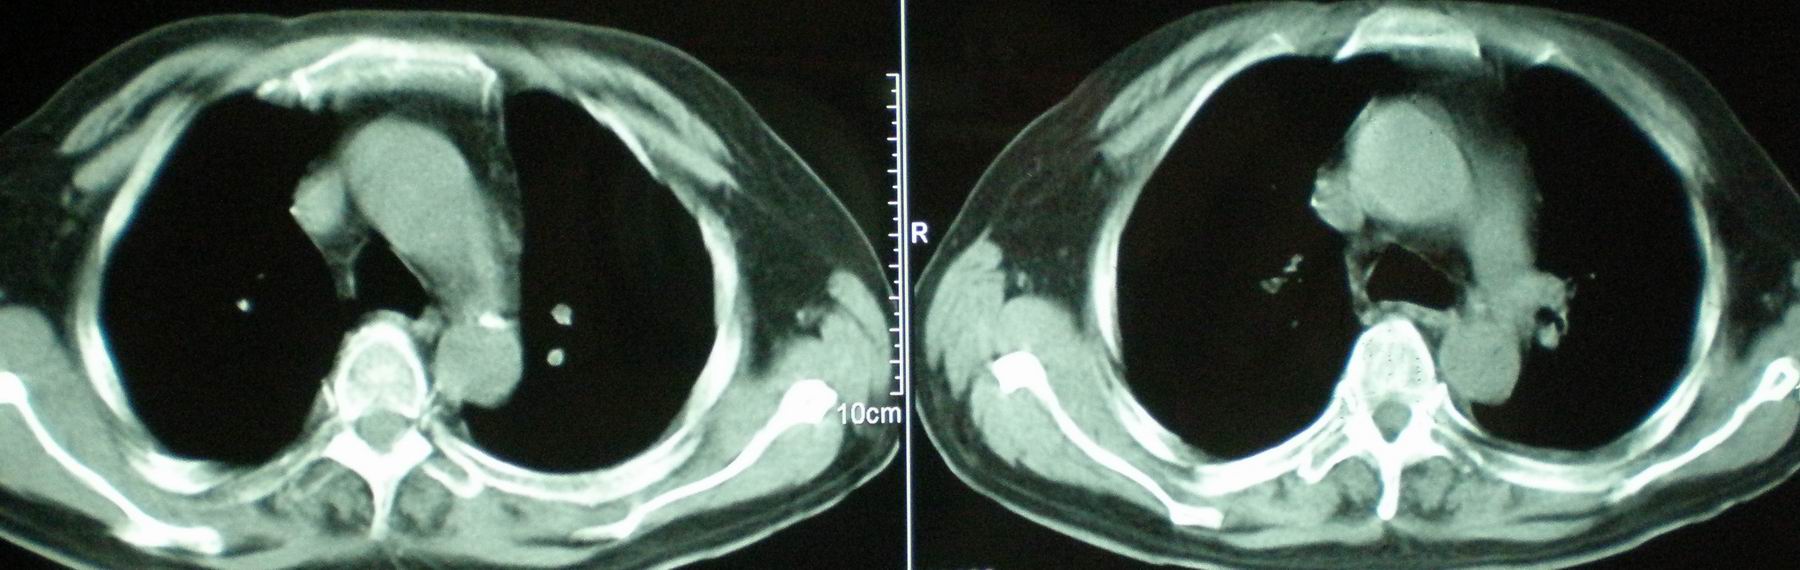

2008年11月18日今天的ct片

2008年9月18日ct片

2008年9月8日ct片:

[face=宋体]显然上级医院进行了抗结核,抗真菌,抗炎等治疗,目前病人肺内病灶基本消失,双侧胸腔积液,右侧积液量有吸收,抗结核一个多月,现在病人疑问,结核的诊断是否有疑义,抗结核是否继续,因为那个毕竟副作用大。[/face]

我仔细看了下病人的出院小结,当时情况危急,诊断里有1型呼衰。心包周围的是脂肪密度。结合三次ct扫描的图象分析,个人认为:1、病人目前肺部病灶基本消失,双侧胸腔内少量积液,抗结核治疗才一个多月,就算是结核,抗结核治疗有效果,为何效果如此好,一点纤维灶的痕迹都没有呢,再就是患者做过气管镜检查及活检、痰检均未找到结核的证据。所以不支持结核的诊断。

2、结合现在的ct片,考虑:肺水肿及真菌感染,双侧胸腔积液。